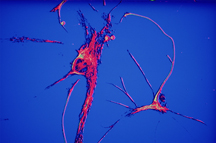

One of their first collaborations and one of her more striking pieces is her interpretation of Alzheimer’s Disease.

“This is very sophisticated stuff. We are interested in specific cells in the brain in very early stages of Alzheimer’s because what we are trying to do is find ways to attenuate the initiation of the disease,” says Bazan.” I believe that is the therapeutic challenge in conquering Alzheimer’s disease.”“I had done several smaller studies just working with the images and the sketches that I had made and they weren’t living to me; they were static,” Nicoll adds. “To see these real examples of actual brain tissue actually experiencing Alzheimer’s or showing signs of Alzheimer’s on a microscopic level is critical to the understanding and development of these pieces. The greatest artists throughout history worked from life. It’s really, really challenging to create an authentic work of art without actually witnessing it in person. It’s one thing if you start it, and then finish it in your studio afterwards. But that experience of seeing it with your own eyes is invaluable. You can’t replicate that.”